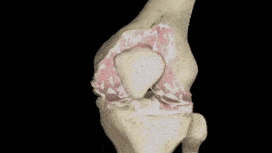

Na kolejnej wizycie dosłownie w ciągu kilku minut zdiagnozował u mnie wtórną chorobę zwyrodnieniową stawów z powikłaniami . Szczerze mówiąc, nie bardzo rozumiałam, co mówił. Wyjaśnił mi coś w niejasny sposób i odesłał do domu z listą tabletek.

Ale największą rzeczą, która mnie zszokowała, była przyczyna mojego bólu. „ To kwestia wieku ” – wyjaśnił mi lekarz. Ale w jakim wieku! Mam dopiero 53 lata i czuję się aktywną, pełną energii mamą moich 18-16-letnich dzieci, a nie starszą panią cierpiącą na chorobę zwyrodnieniową stawów.